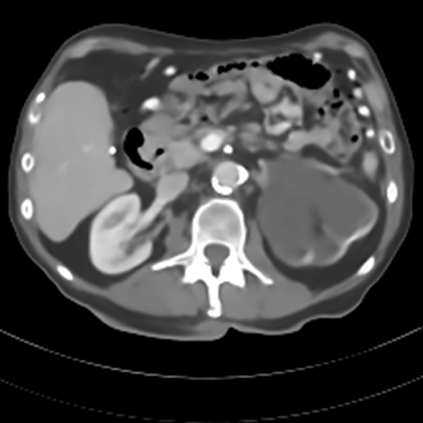

Sparse-view computed tomography (CT) -- using a small number of projections for tomographic reconstruction -- enables much lower radiation dose to patients and accelerated data acquisition. The reconstructed images, however, suffer from strong artifacts, greatly limiting their diagnostic value. Current trends for sparse-view CT turn to the raw data for better information recovery. The resultant dual-domain methods, nonetheless, suffer from secondary artifacts, especially in ultra-sparse view scenarios, and their generalization to other scanners/protocols is greatly limited. A crucial question arises: have the image post-processing methods reached the limit? Our answer is not yet. In this paper, we stick to image post-processing methods due to great flexibility and propose global representation (GloRe) distillation framework for sparse-view CT, termed GloReDi. First, we propose to learn GloRe with Fourier convolution, so each element in GloRe has an image-wide receptive field. Second, unlike methods that only use the full-view images for supervision, we propose to distill GloRe from intermediate-view reconstructed images that are readily available but not explored in previous literature. The success of GloRe distillation is attributed to two key components: representation directional distillation to align the GloRe directions, and band-pass-specific contrastive distillation to gain clinically important details. Extensive experiments demonstrate the superiority of the proposed GloReDi over the state-of-the-art methods, including dual-domain ones. The source code is available at https://github.com/longzilicart/GloReDi.